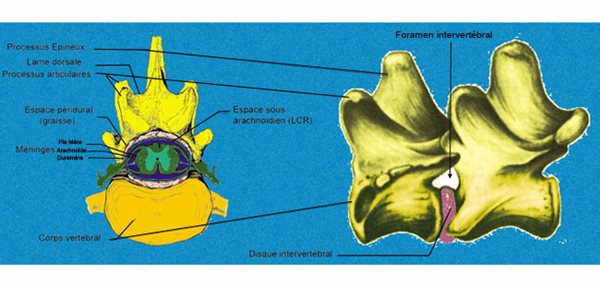

Eléments anatomiques

Le disque intervertébral est un "coussin" de fibrocartilage qui unit les vertèbres par leur partie ventrale qui est le corps vertébral.

Le disque intervertébral est composé de deux parties : un noyau gélifié (le noyau pulpeux) entouré d'un anneau fibreux dont l'épaisseur dorsale est plus faible que l'épaisseur ventrale.